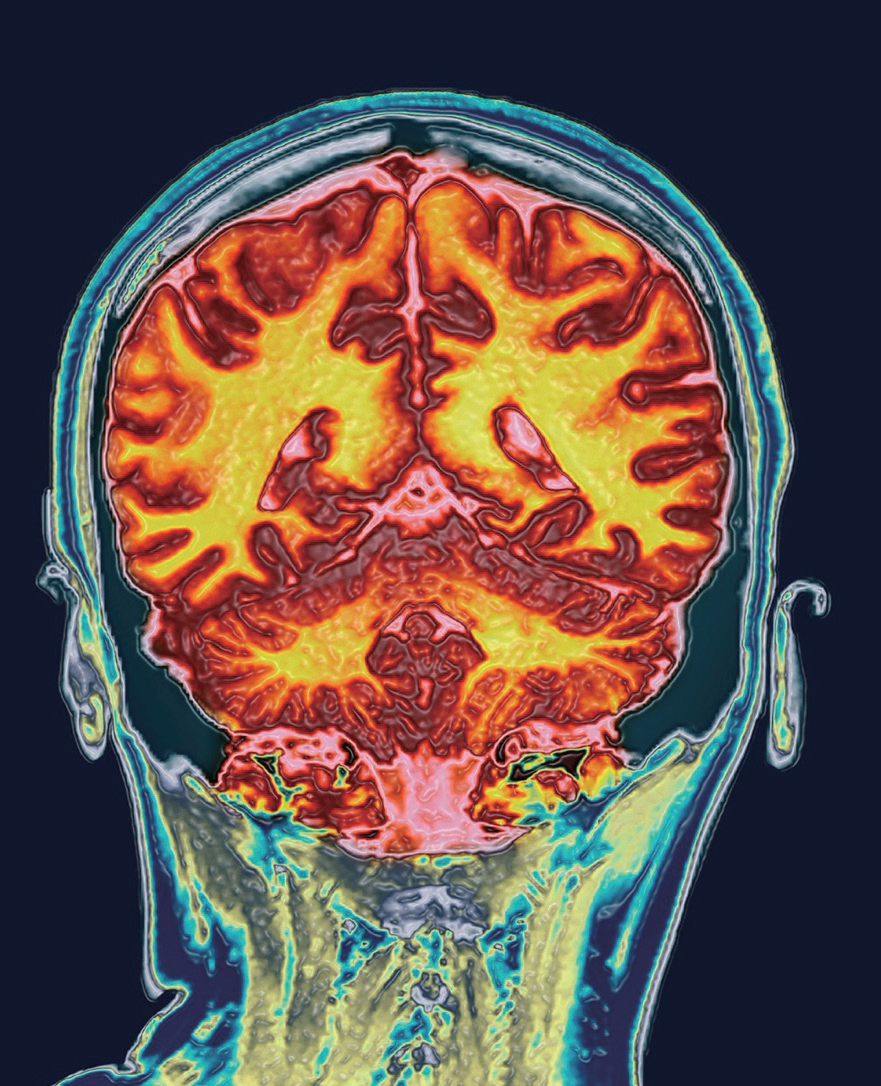

图为32岁绝经前健康女性的颅脑磁共振(MRI)冠状位扫描成像图。《自然-心理健康》(Nature Mental Health)杂志新刊发的一项研究发现,女性大脑特定区域的体积会在生理期发生变化

最近对女性大脑进行的MRI扫描显示,生理期(月经周期)期间性激素水平的起伏会戏剧性地重塑脑中控制情绪、记忆、行为和信息传递效率的区域,而这以约29天为周期的性激素潮起潮落是让生殖器官为女性可能怀孕做好准备。

在发表于《自然-心理健康》杂志的一项研究中,萨赫课题组利用超声波确定了27名女性志愿者精确的排卵时间,这让他们能够在志愿者月经周期内的六个精确时间点采集血液样本,所选的时间点与排卵和血液中的激素水平相关联。随后他们使用超高场强MRI在这六个特定时间点对这27名女性的大脑进行扫描成像。

他们采用的技术比临床常用的核磁共振成像技术更强大,得益于此,萨赫的团队能获得高分辨率的活体大脑影像,而这种分辨率的在过去只有在尸检过程中对大脑直接切片才能获得。

尽管海马体是一个非常小的结构,萨赫团队还是成功观察到,随着海马体的重塑与月经周期同步发生,其不同区域出现了一系列设计精良的变化。海马体外层变厚,灰质随着雌激素水平上升与孕激素水平下降而扩张。但当黄体酮水平升高时,涉及记忆的层结构就会扩大。